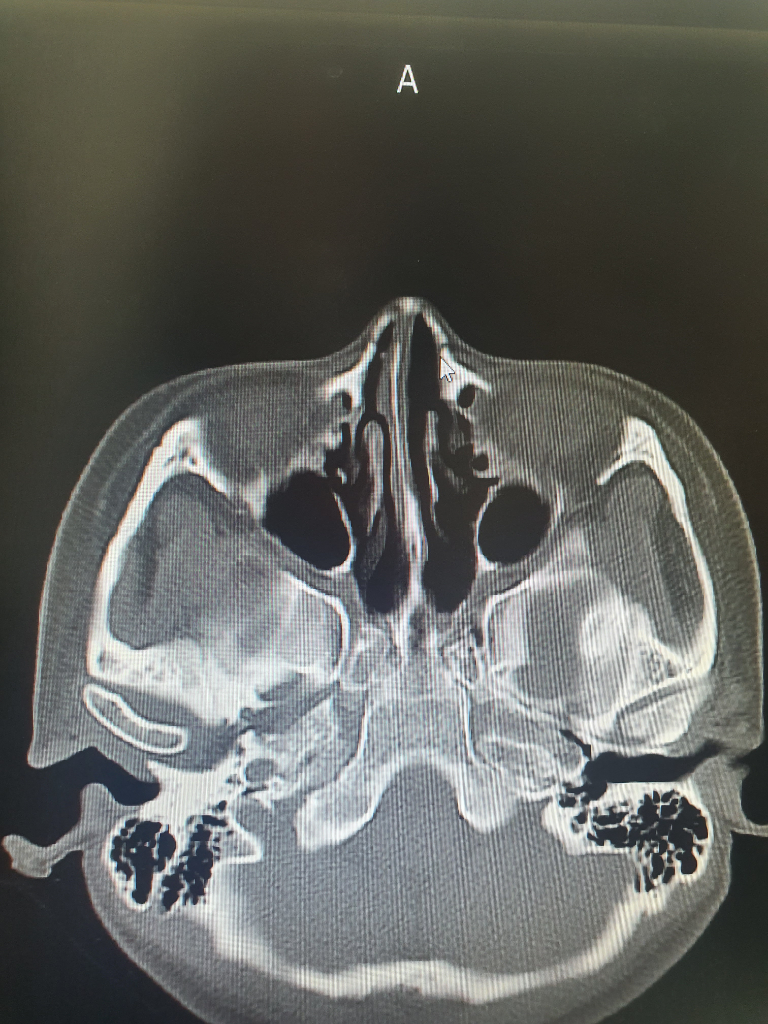

Ct찍은 사진보면 코뼈 재골절된건가요?

제가 작년10월에 오른쪽 코뼈가 부러져서 정복술 수술을받았습니다.

그러고 엊그제 서랍장 손잡이에 부러진곳 정중앙을 부딪혀 코가 또부러진건지 걱정되어 오늘 병원에서 ct및 3dct를 찍었습니다. 선생님께서는 골절은 안보이고 그냥 타박상같다고, 혹시 미세골절이 있더라도 수술할정도는 아니라서 걱정 안해도된다고하셨습니다. 전 처음 코뼈수술한 대학병원에 다시가봐야할지 고민이 되어서요. 사진상 골절소견은 보이지않나요?

이 세사진으로 코뼈 골절을 진단하기는 매우 어렵겠습니다.

해당 병원에 판독지 등을 요청해 보시는 것이 좋겠습니다.

• 올리신 사진의 몇 장 가지고 확실하게 판단하기는 어렵습니다만, 적어도 올리신 사진의 소견에는 코뼈 골절이 따로 보이지 않습니다. 걱정되신다면 수술 받으신 병원에서 재차 진료를 받아보는 것도 괜찮은 방법입니다만 크게 소견에 차이가 있지는 않을 것 같습니다.